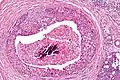

Very low mag. Intermed. mag.

Intermed. mag. Very high mag.